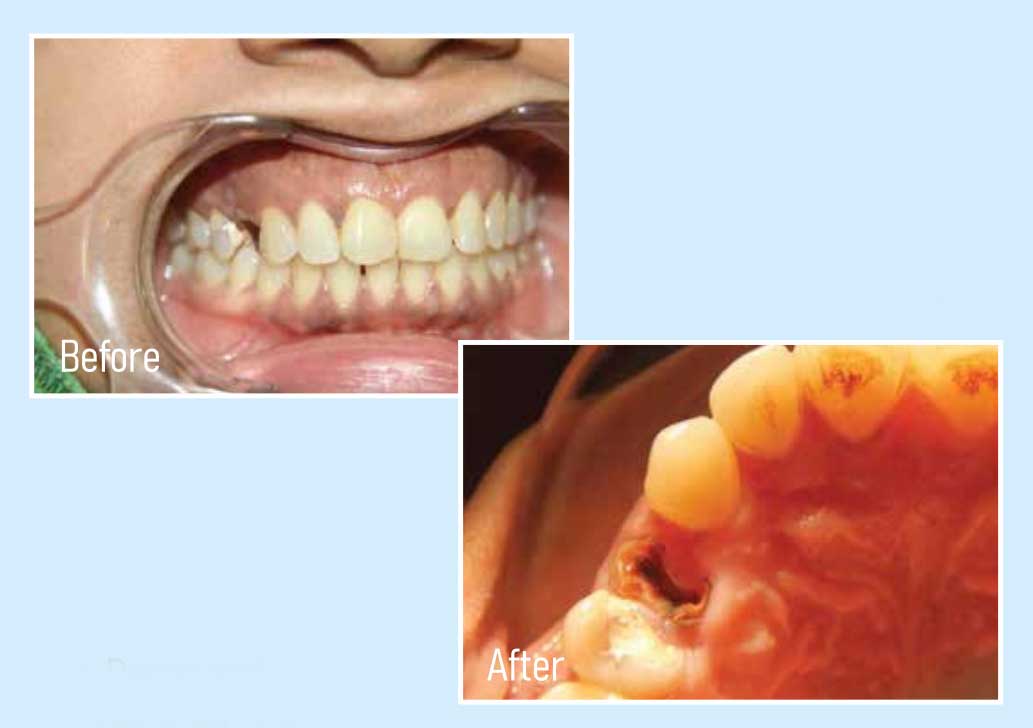

Instantly reverse age with missing teeth the face has a sunken appearance and a person looks much older than he/she on the actually with dental implant this is reverse immediately and a well-balanced natural and radiant smile is gained. This process alone would make one look at least 20 years youngest.

Dental Implant Gallery